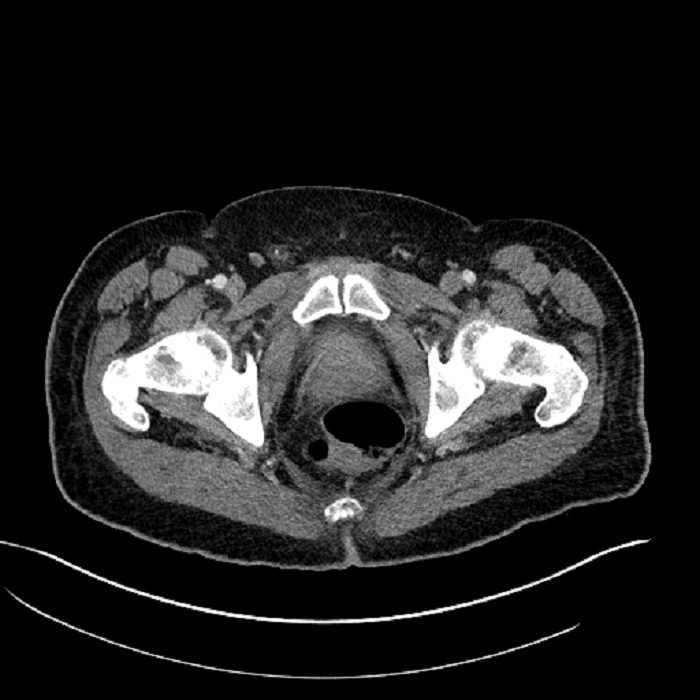

Age: 63

Sex: Male

Indication: Abdominal pain

• High grade stenosis of the left common iliac artery, with the left internal and external iliac arteries remaining patent

• Ankylosis of both sacroiliac joints

Acute sigmoid diverticulitis complicated by a small contained perforation and a large abscess in the right hepatic lobe. Additional small subcapsular abscesses along the anterior margin of the left hepatic lobe.

High grade stenosis of the left common iliac artery. The left external and internal iliac arteries are patent.

Hepatic abscess showing the double target sign with low density internally surrounded by a thin inner enhancing rim (red arrow) and ill-defined outer low density rim (yellow arrow). Blue arrow indicates an internal septation. Red arrows: additional smaller subcapsular abscesses. Red arrow: focal contained perforation associated with diverticulitis.